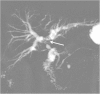

Malignancies of the biliary tract include cholangiocarcinoma, gallbladder cancers and carcinoma of the ampulla of Vater. Biliary tract adenocarcinomas are the second most common primary hepatobiliary cancer. Due to their slow growing nature, non-specific and late symptomatology, these malignancies are often diagnosed in advanced stages with poor prognosis. Apart from incidental discovery of gall bladder carcinoma upon cholecystectomy, early stage biliary tract cancers are now detected with computed tomography (CT) and magnetic resonance imaging (MRI) with magnetic resonance cholangiopancreatography (MRCP). Accurate characterization and staging of these indolent cancers will determine outcome as majority of the patients' are inoperable at the time of presentation. Ultrasound is useful for initial evaluation of the biliary tract and gallbladder masses and in determining the next suitable modality for further evaluation. Multimodality imaging plays an integral role in the management of the biliary tract malignancies. The imaging techniques most useful are MRI with MRCP, endoscopic retrograde cholangiopancreatography (ERCP), endoscopic ultrasound (EUS) and positron emission tomography (PET). In this review we will discuss epidemiology and the role of imaging in detection, characterization and management of the biliary tract malignancies under the three broad categories of cholangiocarcinomas (intra- and extrahepatic), gallbladder cancers and ampullary carcinomas.